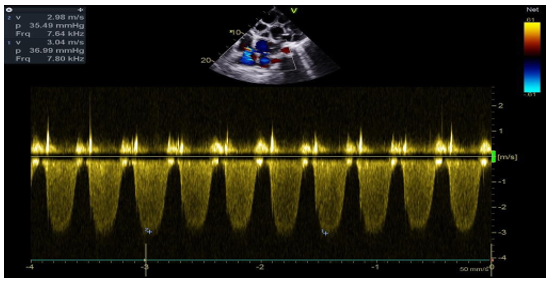

The transthoracic echocardiographic examination revealed (Figures 8 – 18):

- A lobulatedcystic image exerting severe compression on both the right and left cardiac chambers, resulting in hemodynamic disturbance and considerable fluctuation in respiratory flows (Figures 12 – 13,17).

- Grade II tricuspid insufficiency was identified, with an estimated systolic pulmonary arterial pressure of 47 mmHg (calculated as 37 + 10 mmHg), indicating the presence of pulmonary hypertension.